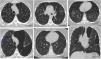

Male smoker with DIP. Axial HRCT slices (images a–c) revealing diffuse ground-glass pulmonary opacities (blue arrows), more extensive in the middle and basal areas, in some locations presenting with some associated central bronchiectasis. Histological section revealing pigmented alveolar macrophages (d) (orange arrow) in areas of emphysema and minimal subpleural interstitial fibrosing component (H&E 10⋅).

The main radiological findings on HRCT include diffuse irregular ground-glass opacities, which can be bilateral, with a basal and peripheral predominance (Fig. 4). In the evolution of the disease, the appearance of small cysts within the ground-glass areas has been described. However, the appearance of reticulation and honeycombing —which would reflect fibrosis— is unusual. Cysts have been associated with dilated bronchioles and alveolar ducts on HRCT.32,33 In follow-up of treated patients with HRCT, the ground-glass opacities should progressively decrease or disappear.33

AEP. An 18-year-old woman admitted to the ICU for acute respiratory failure with AEP diagnostic criteria, in addition to peripheral eosinophilia >15%. The clinical and radiological picture resolves rapidly in two to three days after the administration of boluses of corticosteroids. Axial HRCT slices (images a–c) and coronal reconstruction (image d) revealing extensive bilateral alveolar opacities (blue arrows) associated with septal thickening, mainly at the bases, creating a crazy-paving pattern. Bilateral pleural effusion.